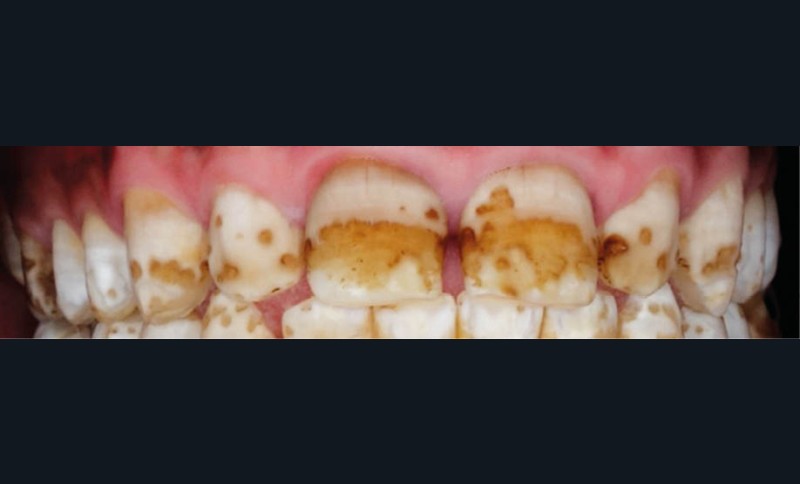

L’émail dentaire, tissu le plus dur et le plus minéralisé du corps humain, peut être affecté par des anomalies génétiques inscrites dans le génome de l’individu, mais également par des facteurs environnementaux. Ces facteurs sont multiples et signent un événement ou une exposition à un xénobiotique au cours de la vie de l’individu. Parmi les atteintes développementales acquises de l’émail, outre la fluorose, figurent les hypominéralisations à type de MIH (Molar Incisor Hypomineralization). Celles-ci sont observées de manière caractéristique sur une ou plusieurs premières molaires permanentes et potentiellement les incisives permanentes éruptant vers l’âge de 6 à 7 ans d’après la description qui en a été faite en 2001 [3] (fig. 1 à 3). La prévalence est importante, la MIH touchant, selon les méta-analyses les plus récentes, plus de 13 % des individus dans le monde, et peut varier selon les études et les pays dans lesquels elles sont menées [4, 5]. Son étiologie est encore incertaine, mais la communauté scientifique s’accorde sur le fait qu’elle serait multifactorielle et notamment en lien avec la survenue d’une hypoxie à la naissance, de fortes fièvres, des épisodes infectieux de la sphère ORL dans la petite enfance ou encore avec une prédisposition génétique [6]. Cette pathologie aurait toujours existé, mais sa prévalence semble être en nette augmentation. Peu d’études ont été réalisées sur cette évolution dans le temps [7].

Les cellules responsables de la synthèse de l’émail, les améloblastes, disparaissant au moment de l’éruption des dents, les défauts de structure et de qualité de l’émail sont irréversibles. L’émail dentaire est ainsi capable d’enregistrer des événements environnementaux ayant eu lieu lors de sa formation. Ces défauts sont donc en quelque sorte le disque dur des contaminations que les améloblastes ont subies. De ce fait, le défaut de minéralisation caractérisant le MIH est le signe d’une exposition environnementale délétère intervenue au cours de la période périnatale (période d’amélogenèse des dents impactées par le MIH), soit environ 5 ans avant leur éruption (fig. 4).

Les leviers à activer dès maintenant pour répondre aux enjeux de santé publique liés à la MIH sont nombreux. C’est d’abord le développement de la collaboration avec les professionnels de santé de la petite enfance. Ceux-ci, dont les médecins généralistes, doivent être sensibilisés au tableau clinique de la MIH – différent de celui de la fluorose ou de l’amélogenèse imparfaite par son caractère asymétrique et sa localisation préférentielle aux molaires et incisives permanentes – afin de favoriser son dépistage et sa prise en charge précoce.

Les enjeux sont très importants. On constate néanmoins que cette maladie est encore mal connue, même des chirurgiens-dentistes. Pour le seul diagnostic, elle est souvent confondue avec la fluorose ou une mauvaise hygiène bucco-dentaire*.